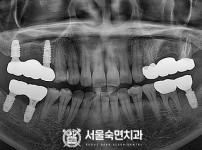

임플란트-전후사진3